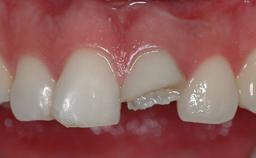

The patient presented with a failing tooth-supported fixed dental prosthesis with cantilever extension replacing the right maxillary central incisor. His chief presenting complaint was poor esthetics, in particular the dark discolored margin around the abutment tooth, the maxillary left central incisor. He reported a history of trauma at a young age, which necessitated the replacement of his maxillary right central incisor as well as root canal therapy of the adjacent left central incisor. The existing prosthesis had been in situ for over 20 years. The initial periapical radiograph displayed good proximal bone levels at the adjacent teeth and a wide incisive canal, which was a concern. The left central incisor presented a very wide root canal treatment with compromised radicular dentin thickness, which was a consideration in the decision between a new tooth-supported fixed dental prosthesis vs. an implant-supported prosthesis. After a lengthy discussion on the risks and benefits of both treatment options, the patient decided on a single-tooth implant replacement.

Esthetic Risk High

Provisional Implant-Supported Prosthesis Prosthodontic margin > 3 mm apical to mucosal margin Prosthodontic margin > 3 mm apical to mucosal margin